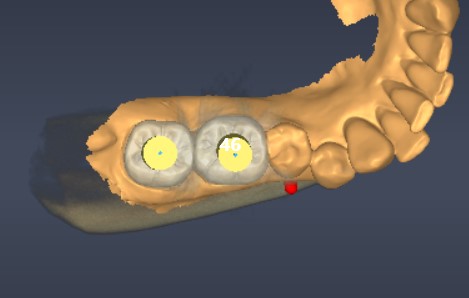

A guided surgical approach was selected, specifically a sleeveless guide, to make use of the precision that it affords in such cases. Dentiq software from 3DII (Dentiq Guide) was used to plan treatment, which allows for precise implant positioning. The surgical guide was then printed on a Phrozen Mini Sonic 8kS, ensuring high accuracy in execution.

Dental implants were then placed using the sleeveless surgical guides. The guided kit from CONELOG® is fantastic, as the screw-in carriers allow for very accurate positioning. After verifying the implant placement, the carriers are replaced and can be used to maintain patency of the implant opening while the graft material is packed into the site.